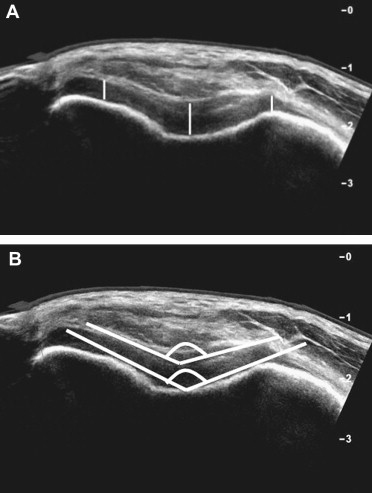

US imaging can partly evaluate the femoropatellar cartilage, its thickness and trochlear femoral and patellar angle [19,20] (Fig. 8).

Fig. 8.

Femoropatellar pain syndrome. Transverse US scans right over the superior patellar pole, with flexed knee, in a normal boy. The image allows evaluation of the femoropatellar cartilage, hypoechoic, thickness (A) (white lines) and trochlear femoral and patellar angle (B).